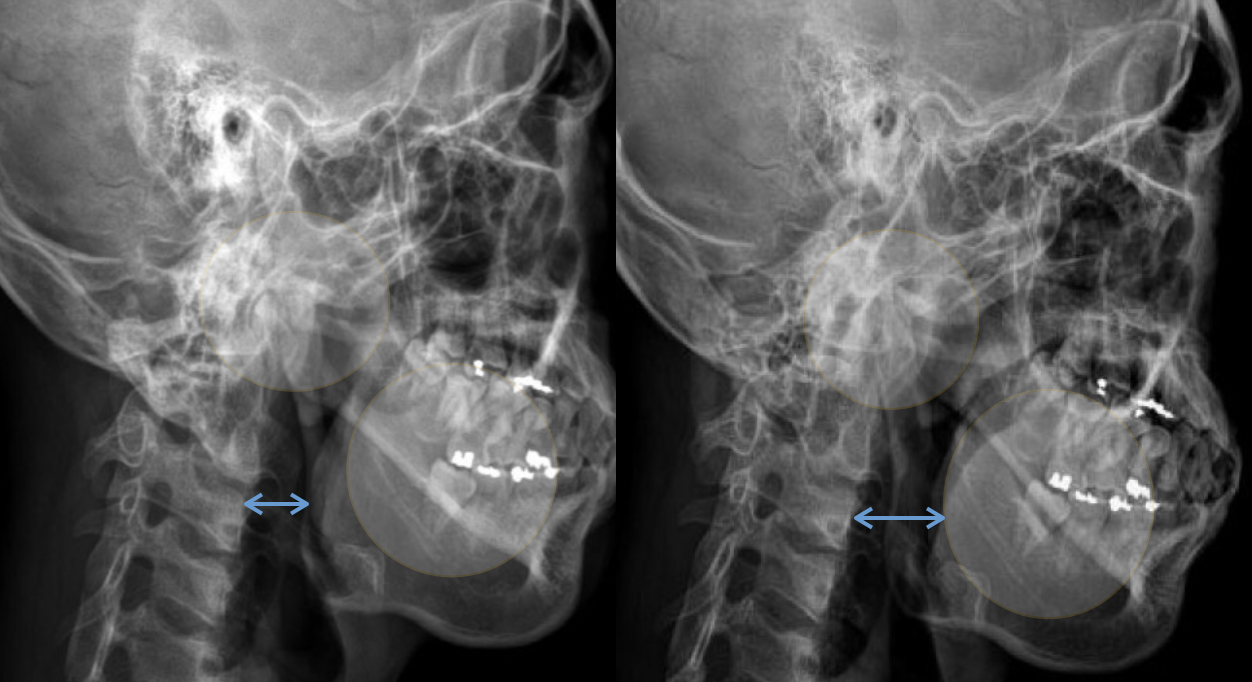

정상 목과 거북목의 두상의 볼록함 차이

결국 거북목이 교정되고 나면 전체적으로 얼굴형태가 입체적으로 바뀌고 납작했던 두상 형태도 위의 그림처럼 볼록함이 증가되면서 입체적인 형태로 교정이 될 것입니다. 사실 전신부정렬 개선을 염두해두고 진행하는 안면비대칭 교정 치료에서는 안면비대칭, 두상비대칭은 당연하게 같이 치료될 수 밖에 없는 부분입니다.